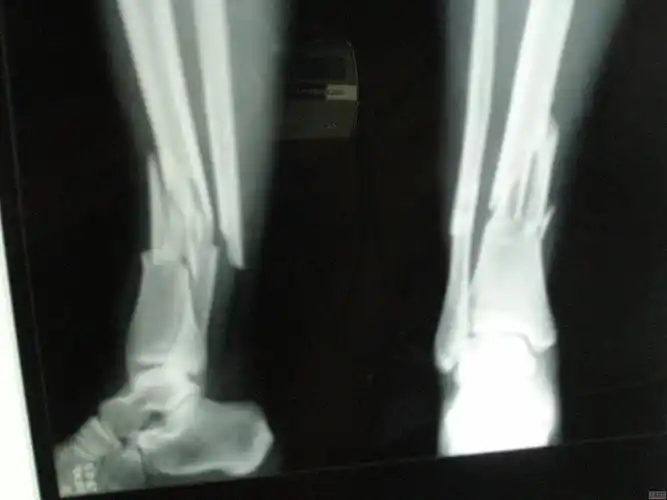

你好,三周前,我从高处跳下,伤到了脚踝,请您帮我看看x光片,看是哪里

左小腿骨折x线片

原创小腿远端粉碎骨折